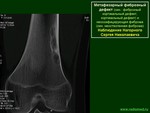

Метафизарный фиброзный дефект кости (МФДК) представляет собой термин, предпочтительно используемый в классификации ВОЗ, поскольку, он является чисто описательным и не отражает какой-либо четкой позиции по все еще остающемуся противоречивым вопросу этио-патогенеза данного процесса. Этим противоречием объясняется наличие различных названий данного вида патологии.

3. Рентгенологическая картина при МФДК весьма характерна и почти всегда позволяет поставить правильный диагноз. Краевой дефект костной ткани расположенный эксцентрически в метафизарных отделах трубчатых костей, никогда не переходит через ростковую зону, имеет ровный или полициклический контур в виде тонкой полоски склероза, отделяющий очаг от совершенно неизмененной окружающей кости и при динамическом наблюдении смещающийся в сторону диафиза.

Учитывая характер локализации и распространенность патологического процесса, по данным рентгенологического исследования, мы выделяем субпериостальную и интракортикальную форму МФДК.

При интракортикальной локализации дефект более глубоко внедряется в костную ткань, как правило, занимая более 1/3 поперечника кости, имеет стенку, отделяющую его от окружающих мягких тканей и чаще всего ячеистую структуру. Данные рентгенологические изменения мы классифицировали как проявления неоссифицирующей фибромы.

Последнее время в диагностике МФДК стала применяться компьютерная томография (КТ) и магнитно-резонансная томография (МРТ), которые позволили визуализировать истинные размеры и структуру патологических очагов, а также их топическое взаимоотношения с нормальными структурами пораженного сегмента кости.

Рентгенологически очаг просветления с чёткими склерозированными границами; вздутие кортикального слоя.

Макроскопически очаг неоссифицируемой фибромы продолговатой формы, локализуется эксцентрично в костномозговом канале и прилежащей кортикальной кости метафизов или метадиафизов, окружён краем реактивной кости.